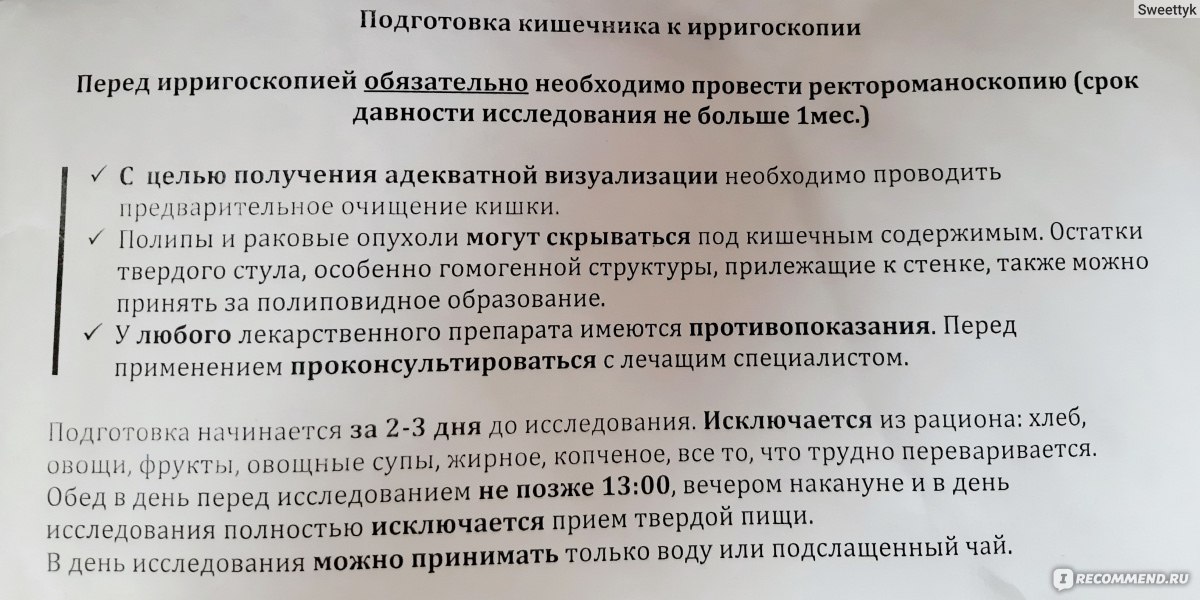

Подготовка к ирригоскопии: необходимые препараты